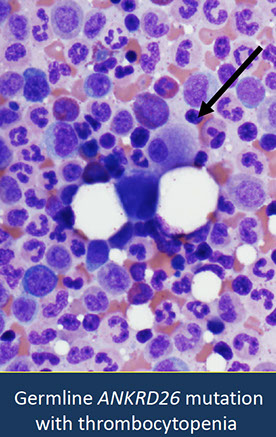

Myeloid neoplasms with germline predisposition and pre-existing platelet disorders

- Myeloid neoplasms with germline RUNX1 mutation

- Myeloid neoplasms with germline ANKRD26 mutation

- Myeloid neoplasms with germline ETV6 mutation